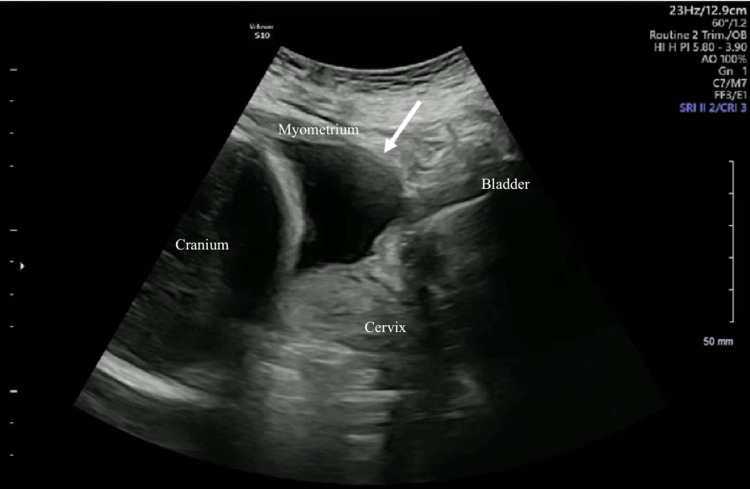

A 39-year-old G11 P3-1-6-4 woman with three previous cesarean deliveries presented at 284/7 weeks for preterm contractions and was admitted to our Labor and Delivery Department for observation. The patient’s vital signs were normal on initial presentation, and pelvic examination showed a closed and long cervix. A category 1 fetal heart rate tracing was noted, and no uterine contractions were detected on tocometry. Of note, the patient had a history of uterine dehiscence in her second cesarean delivery but not at the time of her third cesarean delivery. The second cesarean delivery was performed six years after her first delivery as a scheduled term repeat delivery. The patient was counseled on the risks of short-interval pregnancy; however, she became pregnant eight months after her second delivery and six months after her third delivery. On admission, a maternal-fetal medicine (MFM) ultrasound was performed, which suggested lower uterine segment dehiscence. The myometrium anteriorly was noted to be abruptly thin with minimal visible tissue and bulging of the lower uterine segment anteriorly toward the bladder (Figure 1).

Figure 1. Transabdominal ultrasound of the lower uterine segment.

Transabdominal ultrasound of the lower uterine segment showing the myometrium anteriorly abruptly thinning with only a serosal layer remaining with protrusion of the amniotic sac through this defect in the sagittal view.

This defect measured approximately 4 cm (Figure 2).